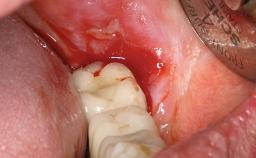

Oral implants are highly successful and offer long-term benefits, especially in the rehabilitation of edentulous patients or patients with oral defects following ablative tumor surgery (Albrektsson and coworkers 1986), and also after radiation therapy (Schiegnitz and coworkers 2014). With the number of implants placed globally going into the millions, implant dentists have observed some rare adverse events. Although carcinogenesis around implants is an exceedingly rare phenomenon, we recently reported about 15 patients treated for carcinomas adjacent to implants at our clinical department over a period of fifteen years (Moergel and coworkers 2014). The following case represents a patient of this cohort; it discusses possible risk factors and makes suggestions for a recall schedule. A 70-year-old woman was referred to our outpatient department for evaluation of a rapidly growing macroscopic alteration of the mucosa in the left mandible.